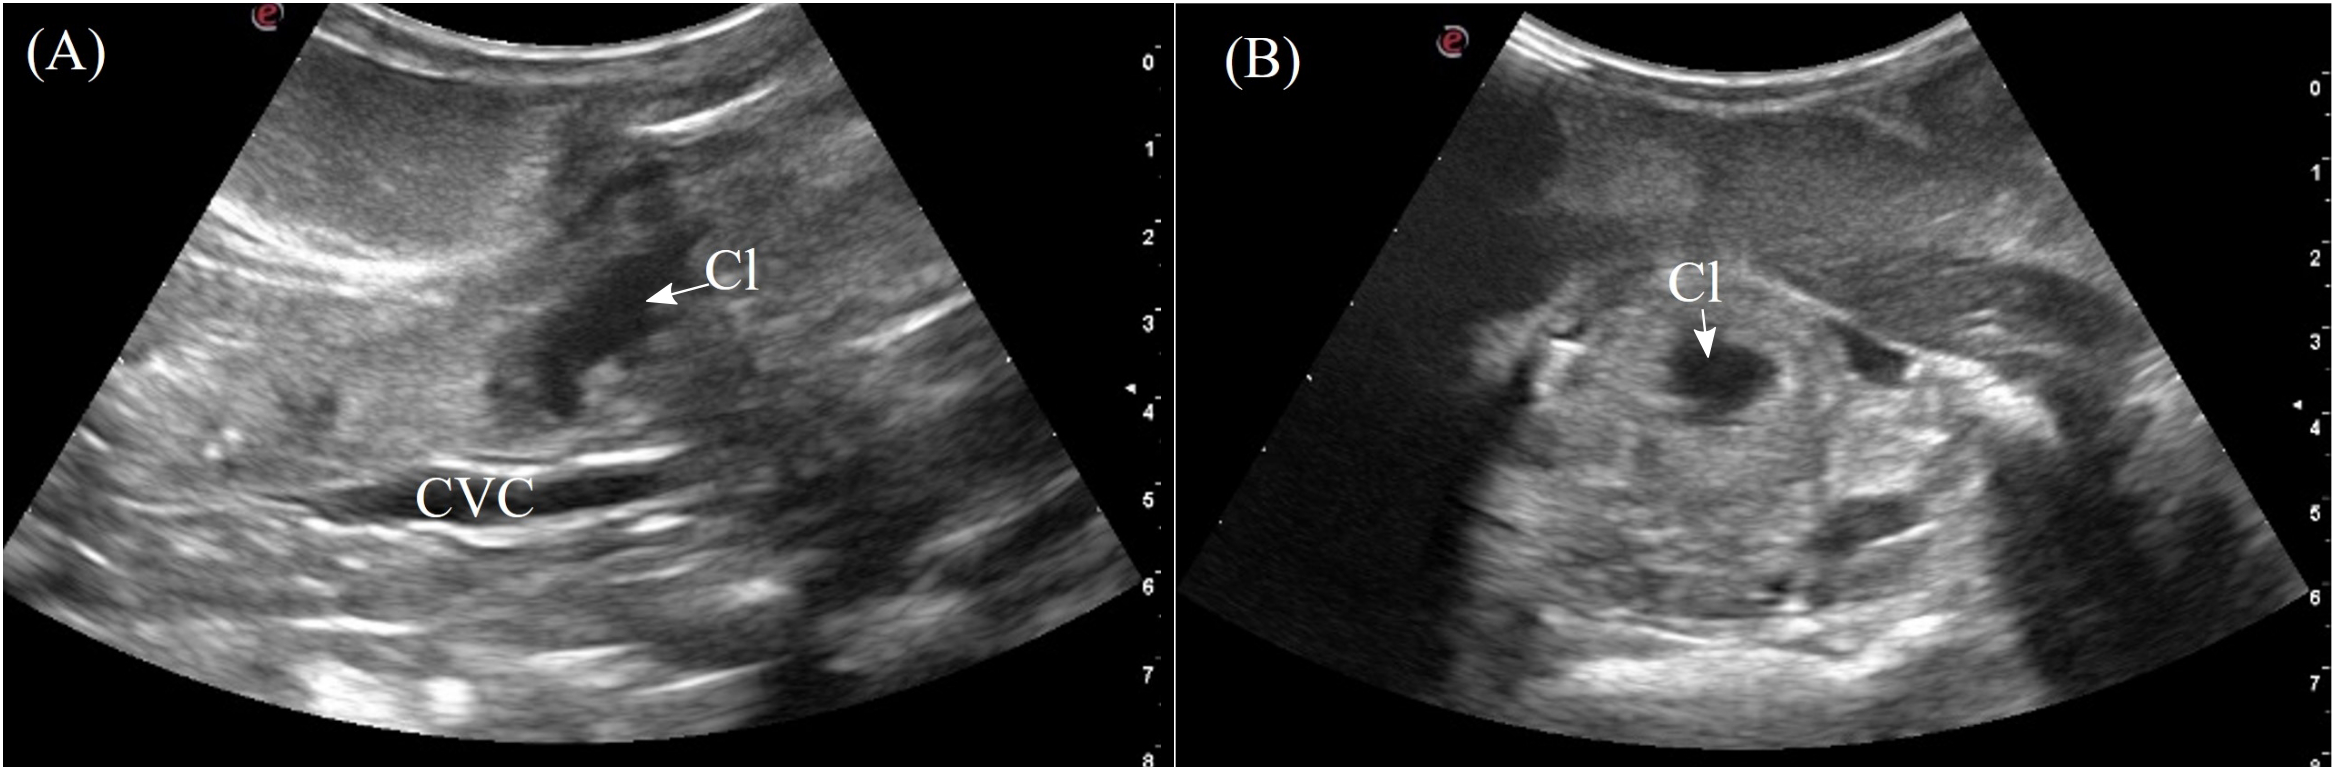

3.3.7 Cloaca

The cloaca was identified in the caudoventral coelom in 5/7 animals when distended with anechoic to hypoechoic fluid. The individual parts of the cloaca i.e. the proctodeum, urodeum and coprodeum might not be able to determine if the compartments were empty. The colorectum and cloaca seemed to be firmly separated by a strong sphincter since urine and feces were clearly confined in two separate compartments. From the lateral flanks, the cloaca was visualized extending into the pelvic canal. In dorsal recumbency, the pelvic portion could be seen by placing the transducer cranial to the vent (Figure 3, transducer position 15). The cloaca had a thick and smooth homogenous wall, slightly more hyperechoic than the adjacent musculature (Figure 12). When large amounts of hyperechoic sediments were present, the far cloacal wall could not be seen.

Figure 12

Ultrasonographic appearance of the cloaca in (A) sagittal and (B) transverse views from the ventral approach in Alligator sinensis. [CVC, caudal vena cava; Cl, cloaca].